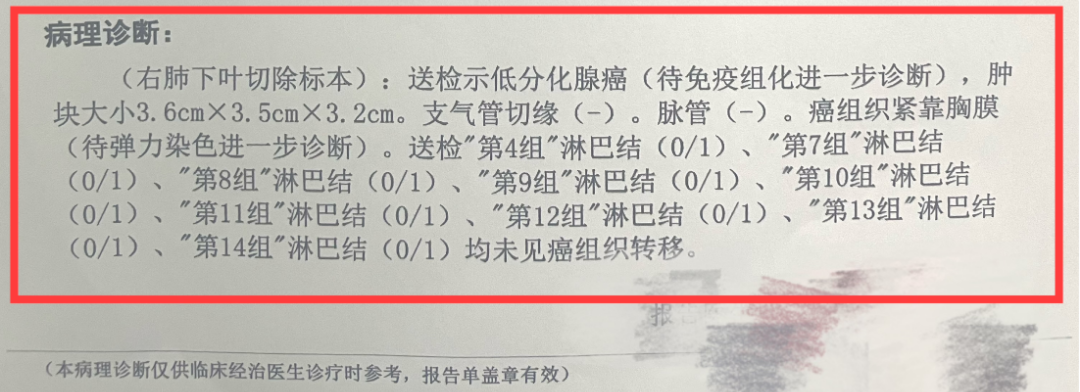

没想到我这么大岁数,切掉一个肺叶的十年后,再次做这么复杂的手术还这么顺利。 D大爷今年72岁,10年前曾行左肺上叶切除+淋巴结清扫术,手术标本病理为腺癌,术后给予了四次化疗。当时的胸部CT即可见右肺上叶小结节影,术后定期复查,病灶缓慢增大,一度略有缩小,此后再次逐渐增大。结合患者一直随访的影像学资料,杨如松院长考虑为右上肺新发恶性肿瘤。 2015年胸部CT 2020年胸部CT 虽然患者及其家属手术的意愿非常强烈,但此手术难度较高,原因在于: 1.患者年龄较高,手术风险大。 2.患者10 年前肺癌手术切除左边肺的一半,肺功能丧失较多。 3.病灶在右上肺的深部,切除有一定的难度。 为了保证患者术后的生活质量,我们不能够做肺的楔形切除这样的简单肺手术,而需要行肺段的切除。 EDDA重建提示病灶位置深 如果放在以前该患者就只能做做放化疗等保守治疗了。幸亏南京胸科医院目前引进了各种国内乃至国际上的先进技术。 如EDDA术前三D成像技术;只有单一3cm长切口的单孔胸腔镜技术;近红外荧光镜肺段、亚肺段精准定位技术等。 有了这些技术,杨如松院长心中有了底气。杨院长根据病人的情况设计手术方案,尽量减轻手术创伤,让接受第二次肺部复杂手术的高龄病人能够耐受,并且在术后能够顺利恢复。 根据术前EDDA三维重建,患者进行了单孔荧光胸腔镜S1a+2a切除术,术中先用ICG反染法确定段间面,再用膨胀萎陷法印证段间面,这保证了手术切除的精准性。 患者术中快速病理为贴壁型腺癌,这也印证了杨如松院长术前对患者肺结节良恶性的判断。 术后5天,D大爷非常顺利的出院了。出院前开心的窦大爷连声感谢杨如松院长:没想到我这么大岁数,切掉一个肺叶的十年后,再次做这么复杂的手术还这么顺利,谢谢、谢谢! 基本情况